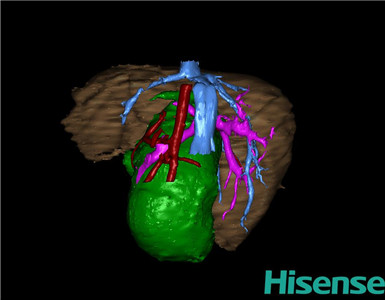

将0.625mm双源薄层CT资料的静脉期和动脉期Dicom格式文件导入海信CAS系统。

通过调节窗宽窗位调整CT序号,对肝实质,胆囊,下腔静脉,肿瘤,肝动脉、门静脉及肝静脉等进行三维重建;系统自动计算肝脏体积。

术前三维重建:

重建图片